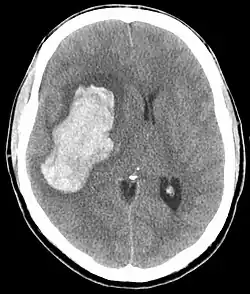

CT scan depicting intracranial hemorrhage, a possible complication of hypertensive emergency. Patients with spontaneous intracranial hemorrhage present with newfound headache and neurologic deficits.

In the brain, hypertensive encephalopathy - characterized by hypertension, altered mental status, and swelling of the optic disc - is a manifestation of the dysfunction of cerebral autoregulation. Cerebral autoregulation is the ability of the blood vessels in the brain to maintain a constant blood flow. People with chronic hypertension can tolerate higher arterial pressure before their autoregulation system is disrupted. Hypertensives also have an increased cerebrovascular resistance which puts them at greater risk of developing cerebral ischemia if the blood flow decreases into a normotensive range. On the other hand, sudden or rapid rises in blood pressure may cause hyperperfusion and increased cerebral blood flow, causing increased intracranial pressure and cerebral edema, with increased risk of intracranial bleeding.[7]